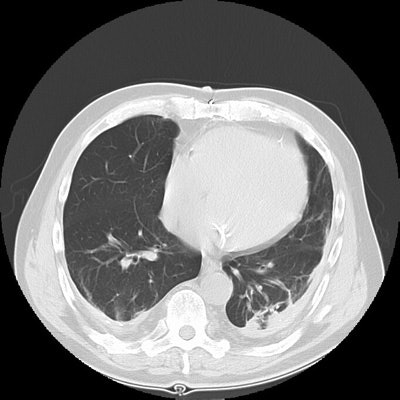

Rounded atelectasis:

The images show bilateral posterior pleural thickening. Within the left posterior lung a rounded pleural based mass-like opacity into which lung markings radiate can be identified. The left major fissure is displaced posteriorly. The lesion has remained stable for many years. The findings are consistent with rounded atelectasis. (Click small images to enlarge)